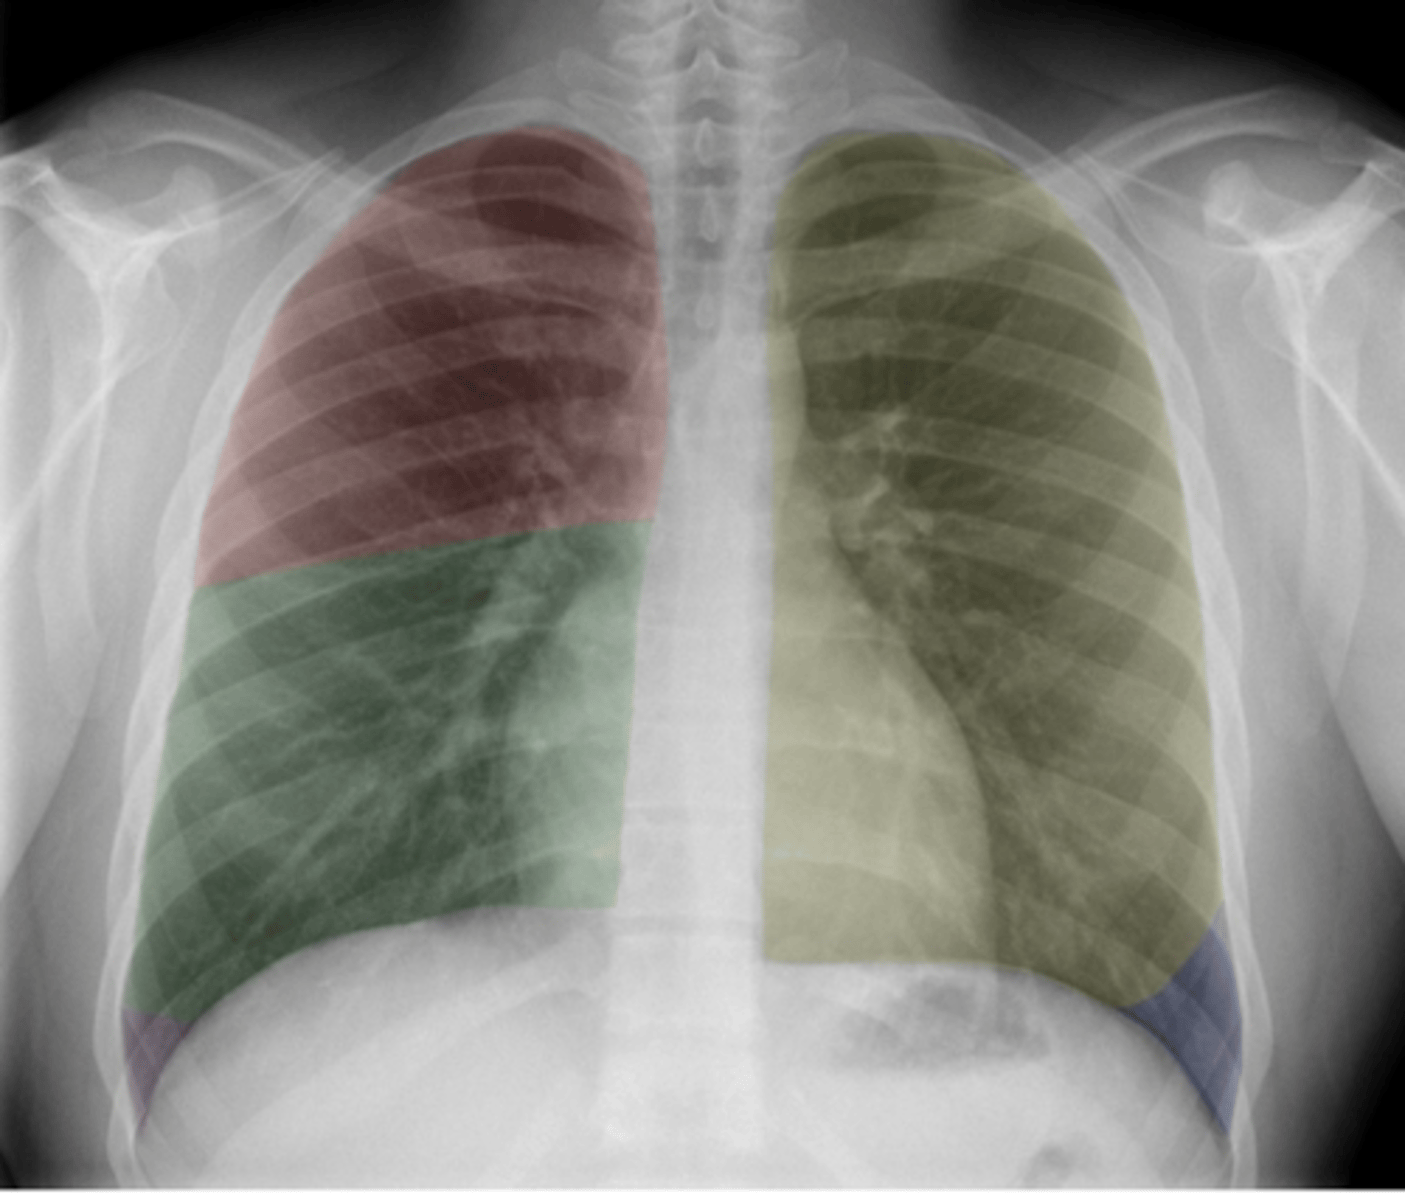

ID lobes of lungs on back (anterior)

•Red: Right upper lobe (RUL)

•Green: Right middle lobe (RML)

•Purple: Right lower lobe (RLL)

•Yellow: Left upper lobe (LUL)

•Blue: Left lower lobe (LLL)

<p>•Red: Right upper lobe (RUL)</p><p>•Green: Right middle lobe (RML)</p><p>•Purple: Right lower lobe (RLL)</p><p>•Yellow: Left upper lobe (LUL)</p><p>•Blue: Left lower lobe (LLL)</p>